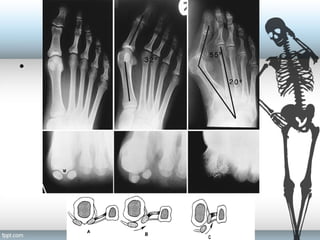

IMA (normal <9°) [8-9]

HVA (normal <15°) [15-20]

DMAA (normal <10°) [10-15]

Hallux

valgus

angle

Intermetatarsal

Distal

metatarsal

articular

Measure Angles

–Hallux Valgus angle:

Intersection of longitudinal axis

of 1st MT and proximal

phalanx. Normal < 150

–Intermetatarsal angle

Intersection of 1st and 2nd

MT. Normal < 90

; increased

with metatarsus primus varus

Radiographic measurements

• Distal Metatarsal Articular Angle(DMMA)

Defines the relationship of the distal articular

surface of the 1st MT to the longitudinal axis.

Quantities the magnitude of lateral slope of

articular surface.

With subluxation, the articular surface deviates

laterally in relationship to the 1st Metatarsal.

Usually < 60

.